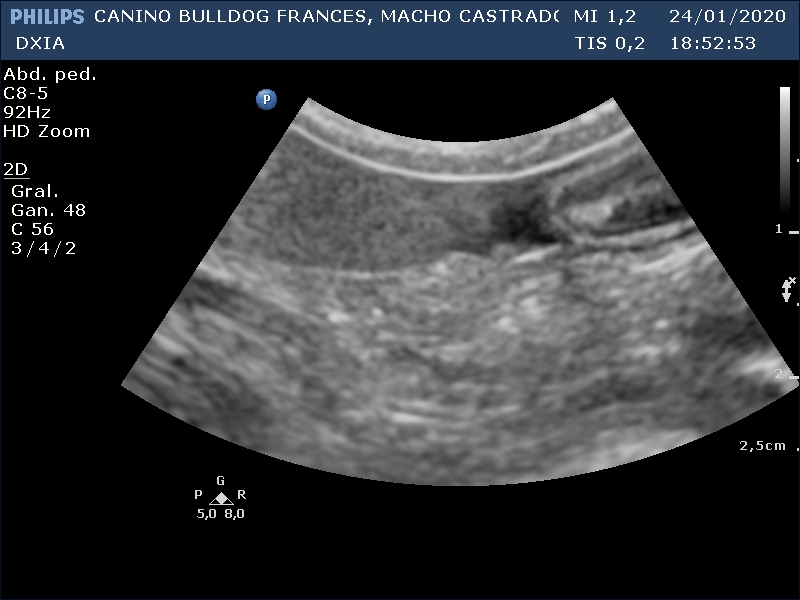

RONY

Del informe ecográfico de Rony se destaca la existencia de varias alteraciones:

Leve presencia de líquido libre abdominal anecogénico

Próstata disminuida de tamaño (castrado recientemente) pero heterogénea

Neoformación en la que se observa estructura en capas en su zona dorsal. Se realiza PAF ecoguiada.